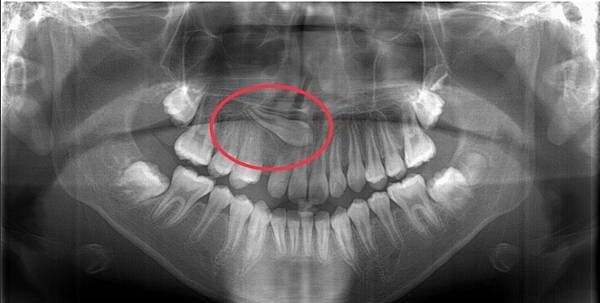

第三種是「埋伏齒」,陳怡如醫師提醒家長,每晚幫小孩刷牙、或是小孩自己刷牙但家長幫忙確認清潔與否時,可以注意對稱位置的牙齒是否發育一致,陳怡如提醒,牙的左右側萌發進度有一定的關聯性,如果相同位置的左邊已經換牙,但是右邊卻遲遲還是乳牙,或是乳牙已經掉了、卻不見恆牙冒出頭等等,家長就要特別注意,儘早帶小孩回診牙醫,以確定是不是該長出來的牙齒因牙胚位置異常而成了「埋伏齒」,曾有小六學生單側犬齒遲遲未萌發,一照x光才發現這顆犬齒已橫移到門牙上方,若硬要將長歪的犬齒拉正則會犧牲門牙,最終不得已只好手術拔掉犬齒,但陳怡如強調,這位患者若早在二年級的時候就回診,當時長歪的犬齒牙根長度未完全長好、角度也還沒這麼偏,還有機會提早透過矯正的方式讓犬齒轉向,由此可見即早發現、即早治療的重要性。不過也有家長反應小孩的換牙期很長,往往忘記哪顆換過、哪顆還沒換,為了幫助家長提高辨識能力,陳怡如教大家一個簡單的方法,就是乳牙比較小顆、比較白,也就是說恆牙相對較大顆、天生也比較黃。

患者單側犬齒遲未萌發,最終只能開刀拔除